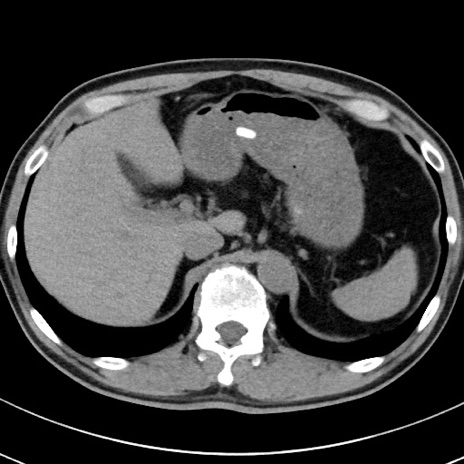

【腹部TIPS】症例29 参考症例 CT(横断像)

症例

70歳代男性